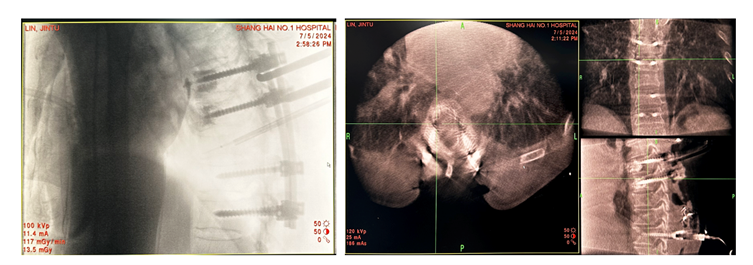

精准手术方案:后路减压固定+分离手术+病灶射频消融。患者为肺癌晚期,经影像学证实T6-9椎体呈现不同程度的骨质破坏。此次手术方案考虑到多个椎体的不同类型及不同程度的骨质破坏,特别是胸椎T8伴有压缩性骨折且侵犯椎管。通过仔细全面的术前评估,我们为患者制定了个性化的手术方案,对于T6、T7和T9椎体,采用了射频消融技术,精准靶向骨转移病灶,有效地控制了局部肿瘤进展,同时减少了不必要的组织损伤。对于T8椎体,考虑到压缩性骨折及椎管侵犯,我们进行了后路减压固定+分离手术,减轻了神经压迫,恢复了椎体稳定性,并配合椎体病灶消融,以确保治疗效果的最大化。这种精细化的手术方案,不仅充分处理了病灶,还最大程度减少了手术创伤,为患者提供了更为安全的治疗选择,术后恢复良好。

术中情况

手术在O臂引导下顺利进行,通过实时影像引导精确定位和操作,我们在术中准确地对病灶区域进行了射频消融,确保了病灶的彻底消融,并避免了周围正常组织的损伤。椎体置钉过程中,O臂影像帮助我们确保了固定的稳定性和精确性。随后,对T8病灶进行了椎板减压及分离手术,进一步消除了压迫,恢复了脊柱的功能。

通过本例肺癌多节段脊柱转移的治疗,我们深刻体会到精准医疗与多学科合作在复杂疾病管理中的重要性。手术过程中,通过O臂引导实现了精准的椎体病灶消融与椎体置钉,确保了手术的高效性与安全性,尤其是在T8椎体的压缩性骨折及椎管侵犯的治疗中,后路减压固定和分离手术有效解决了神经压迫问题,恢复了脊柱的稳定性。